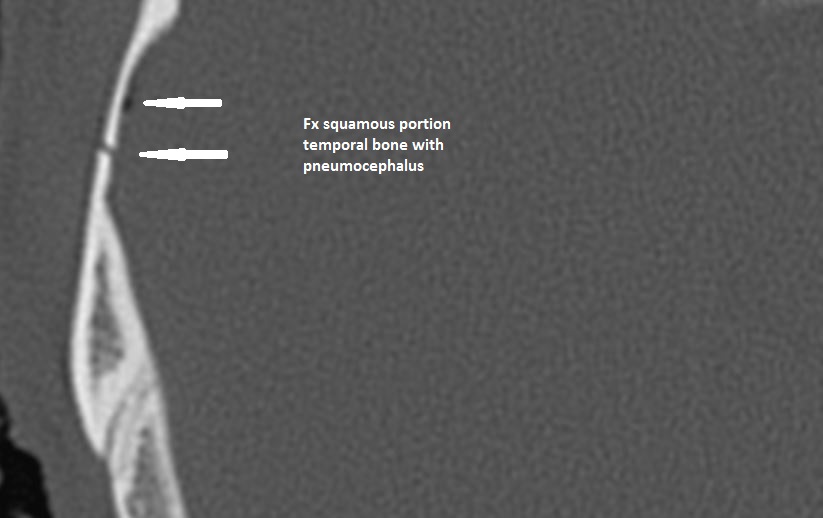

Right Temporal Bone

Left Temporal Bone